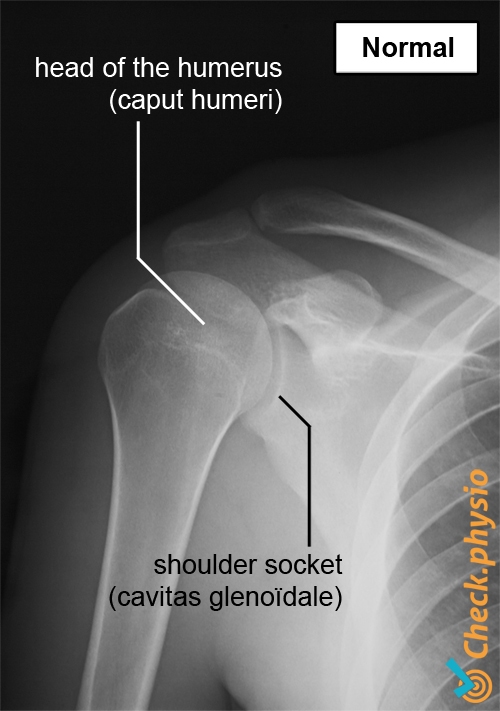

The shoulder consists of a ball and socket, among other structures. Contrary to what you might expect, the shoulder socket is actually only a very small socket in relation to the much larger humeral head (the upper arm bone). This gives us great mobility of the shoulder, but also makes the joint unstable. This instability is largely compensated by the muscles in the shoulder, and to a lesser extent the ligaments located around the joint.

If a subluxed shoulder is suspected, further X-ray examinations will be performed. An X-ray can reveal the direction of subluxation and may potentially also rule out further injury such as bone breaks, muscle tears or damage to the joint capsule.